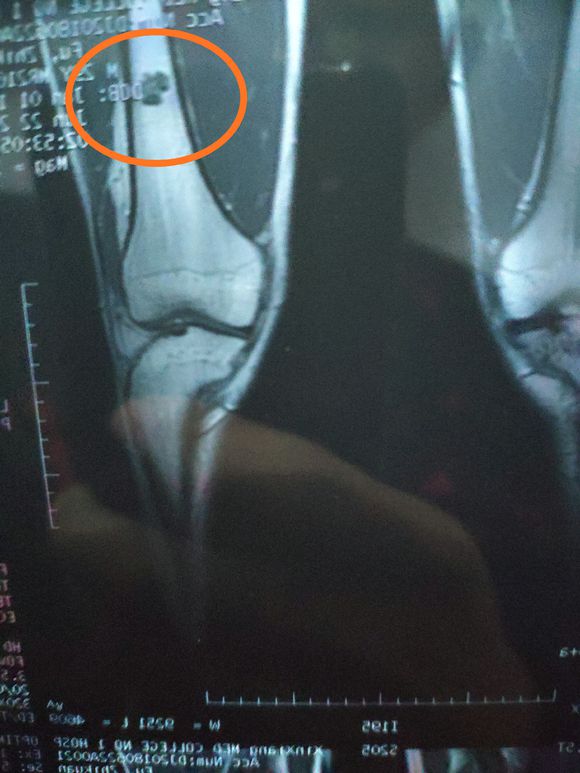

女儿14岁,明天做截肢手术。医生让从髋关节处截,想保留个七八公分。问问大神们髋关节以下留七八公分能用常规的假肢吗? ...